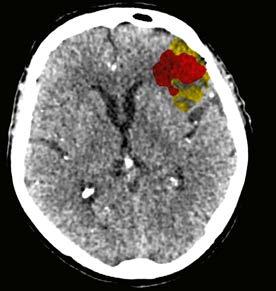

System, natürlich datenschutzkonform, gespeist haben. Die KI hat nach vielen Iterationen gelernt, auffällige von unauffälligen CT/MRT-Befunden zu unterscheiden. Dem Radiologen werden die Auffälligkeiten farblich markiert angezeigt. Gleichzeitig können wir mit hoher Sicherheit einen Normalbefund erkennen. Dies beschleunigt die Befundung, minimiert die Fehlerquote und erhöht gleichzeitig die Patientensicherheit.